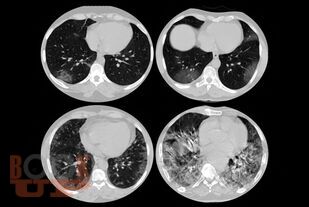

Пособие подготовлено в соответствии с требованиями ФГОС ВО по специальности 31.05.01 Лечебное дело, действующего учебного плана и рабочей программы (2020 г.) для изучения дисциплины «Неврология, нейрохирургия». В нем излагаются современные представления об этиопатогенезе новой коронавирусной инфекции COVID-19, подходы к ее диагностике и лечению, а также клинические особенности поражения нервной системы.

Отдельно рассмотрена организация медицинской помощи пациентам неврологического профиля в условиях распространения COVID-19. Уровень изложения материала соответствует современным требованиям и позволяет оптимизировать организацию и управление самостоятельной работой обучающихся. Пособие содержит тестовые задания и ситуационные задачи, которые помогут в изучении неврологической аспектов COVID-19.